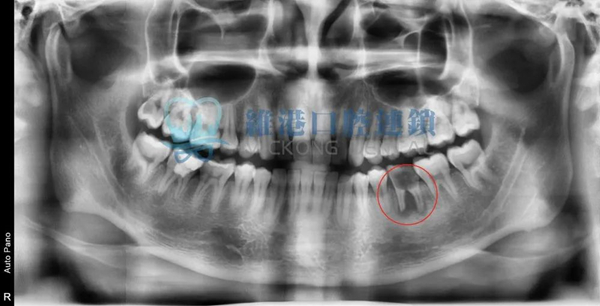

中重度案例